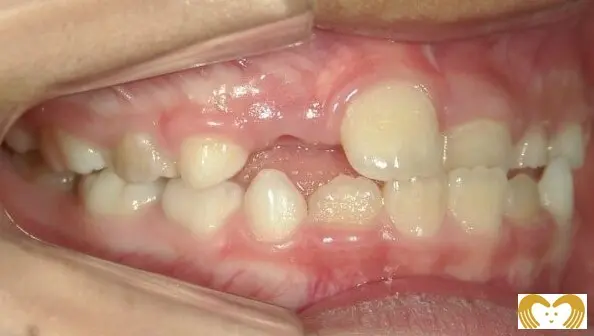

症例02:交叉咬合

《Before》

《After》

- 年齢:

- 7~12歳

- 性別:

- 女の子

- 治療内容:

- ネオキャップシステムによる、交叉咬合の治療

- 治療回数・期間:

- 約5年間

- 治療費:

- 495,000円(税込)

- リスク:

- 取り外し可能な装置の為、治療の効果が使用頻度に左右されます。